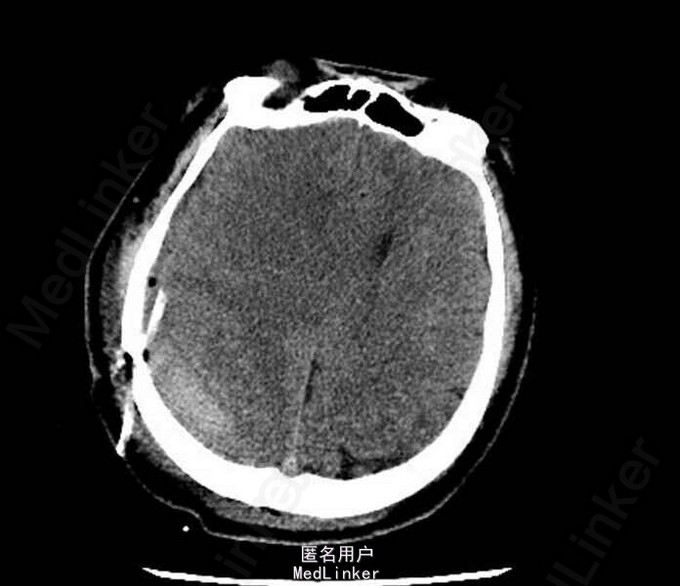

查体:神清,遵嘱,E4V5M6,双侧瞳孔等大正圆,对光敏; 头颅MRI提示:右侧额颞顶部硬膜下血肿(急性期),中线左移位约9.2mm。

术后患者症状明显改善,复查头颅CT提示血肿清除满意。